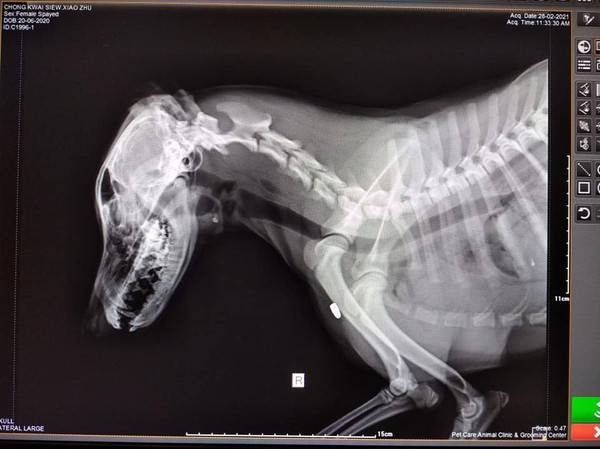

▲子彈卡在狗狗的前肢。(圖/翻攝自臉書)

鍾女指出,回到店裡發現狗狗中槍,連忙找了一間有完善設備的寵物醫院,照3次X光才照出子彈,讓她心痛表示,「我的狗並沒有攻擊誰,沒有亂闖亂吠」,「為什麼要亂開槍射我的狗」。

根據馬來西亞《星報》報導,中槍的狗狗是8個月大的米克斯,警方從屍體中取出長1公分、疑似空氣槍子彈,調查結果顯示,子彈從第4、第5支肋骨射入,貫穿肺部及心臟,彈頭卡在右前肢肌肉上,目前依當地法規「虐待導致動物致死或傷殘罪」偵辦中。